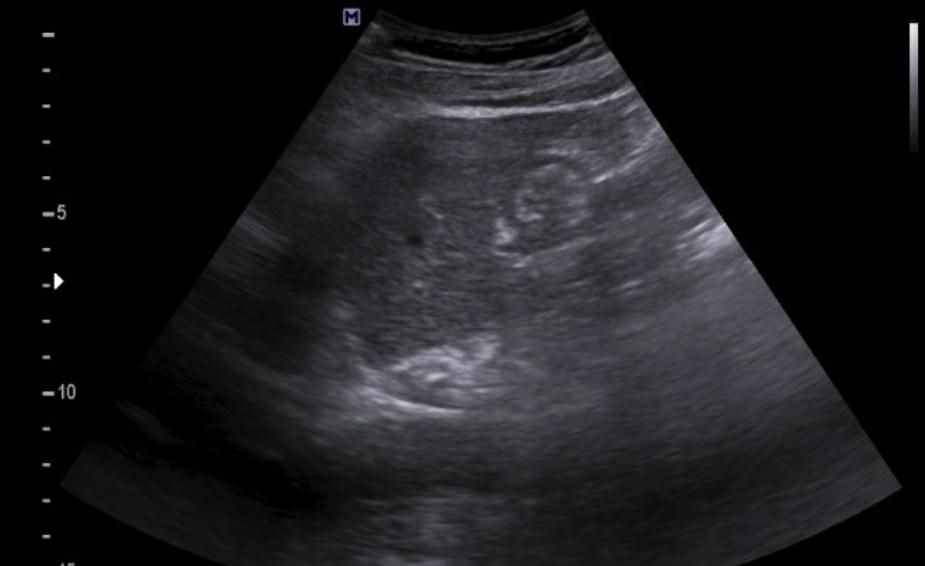

간에 혹이 있는건가요? 초음파 사진 봐주세요

간에 혹이 있는건지 맞다면 크기나 모양이 혈종인지 아이면 암으로 의심이 되는지 초음파 사진 봐주세요...ㅜㅜㅜ꼭 답변 부탁드립니다

• 1번 째 사진

간 초음파로만 봐서는 약간의 지방간이 관찰되지만 혈종으로 의심되지는

않으며 사진 우측에 보이는 동그란 부분은 장의 단면이 관찰되었을 가능성이

높은 것으로 보입니다